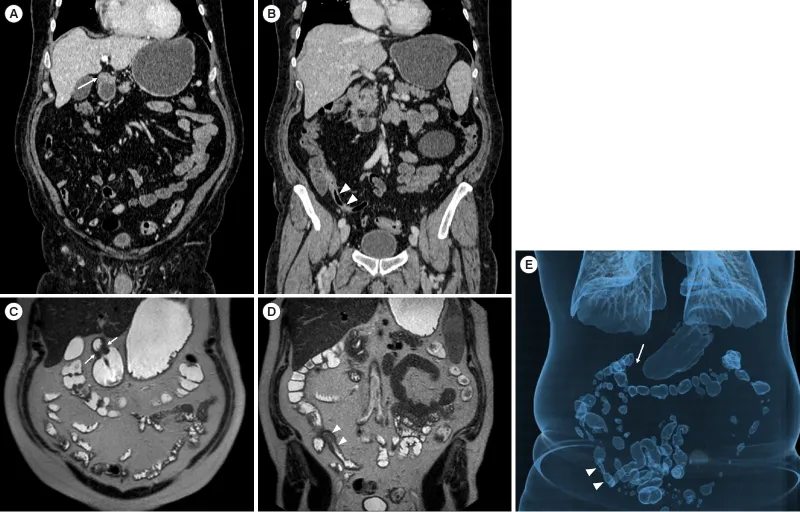

- Dx: CT with oral/rectal contrast.